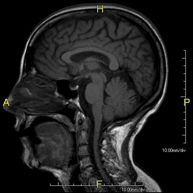

- Neuroradiology

- Brain MRI (cranial)

This non-invasive diagnostic procedure uses an electromagnetic field and radio waves (from a transmitter and receiver) to acquire high-definition anatomical images of the brain. It is a radiation-free procedure. Indicated for: vascular problems, memory loss, epilepsy, headache, malformations, suspected tumour, meningitis.